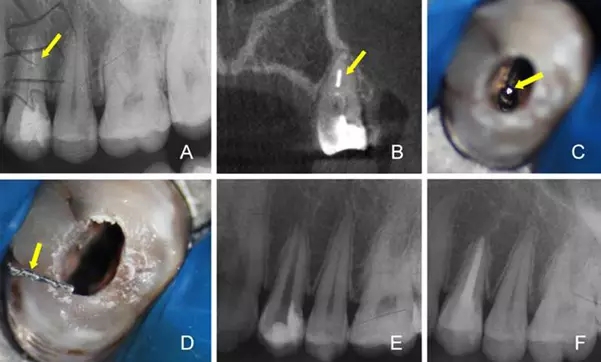

A:術(shù)前X線根尖片 B:術(shù)前CBCT定位折斷器械位置 C:顯微鏡下尋找折斷器械 D:顯微鏡下隱裂紋清晰可見(jiàn) E:術(shù)后X線根尖片 F:一年后復(fù)查X線根尖片

4.根管內(nèi)折斷器械的取出

器械折斷于根管內(nèi)是根管治療主要并發(fā)癥之一,有效取出根管內(nèi)折斷器械可提高根管治療的臨床療效。傳統(tǒng)方法取出率低,并且容易發(fā)生側(cè)穿或?qū)⒄蹟嗥餍低葡蚋飧钐?。手術(shù)顯微鏡在折斷器械取出過(guò)程中能提供良好的視野,充分暴露折斷器械,是根管內(nèi)折斷器械順利取出的必要條件。顯微鏡輔助超聲技術(shù)能安全、有效取出大部分折斷器械,是目前最常用的折斷器械取出方法[7,8]。首先,術(shù)前要通過(guò)研讀X線片對(duì)折斷器械的類(lèi)型、位置、長(zhǎng)度和根管的彎曲度、厚度進(jìn)行判斷,以初步評(píng)估取出根管內(nèi)折斷器械的可行性及預(yù)后。在手術(shù)顯微鏡下,建立直線通道至折斷器械冠方,使用超聲器械逐步去除折斷器械四周的牙本質(zhì),游離折斷器械的中上部,使折斷器械上段與根管壁間有一定的間隙。在此過(guò)程中要盡可能少磨除過(guò)多牙本質(zhì),防止降低牙體的抗折強(qiáng)度,造成根管壁的穿孔。當(dāng)逆時(shí)針圍繞折斷器械振動(dòng)時(shí),多數(shù)情況下折斷器械會(huì)逐漸松動(dòng),隨沖洗液漂出彈出[9]。